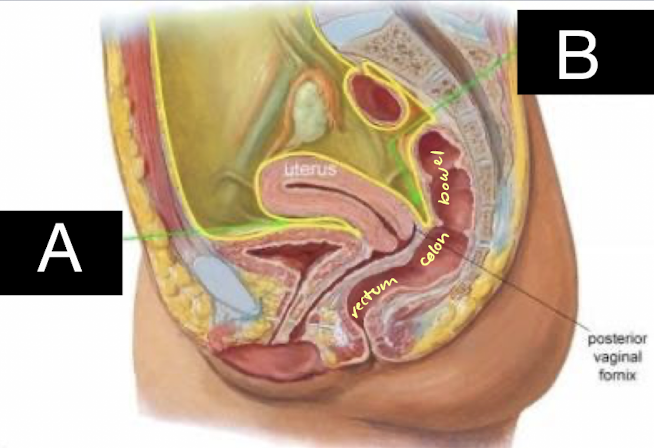

uterus

located in lesser (true) pelvis

posterior to bladder in vesicouterine pouch

anterior to colon/rectum in rectouterine pouch (aka Pouch of Douglas)

what is A pointing to?

vesicouterine pouch

what is B pointing to?

rectouterine pouch (aka Pouch of Douglas)

potential spaces where fluid may accumulate

anterior cul-de-sac (vesicouterine pouch)

in front of uterus

posterior cul-de-sac (pouch of Douglas/rectouterine space)

behind uterus

FF often accumulates here b/c of gravity and bigger space

Space of Retzius (retropubic space)

in front of bladder

“between anterior bladder and pubic symphysis”